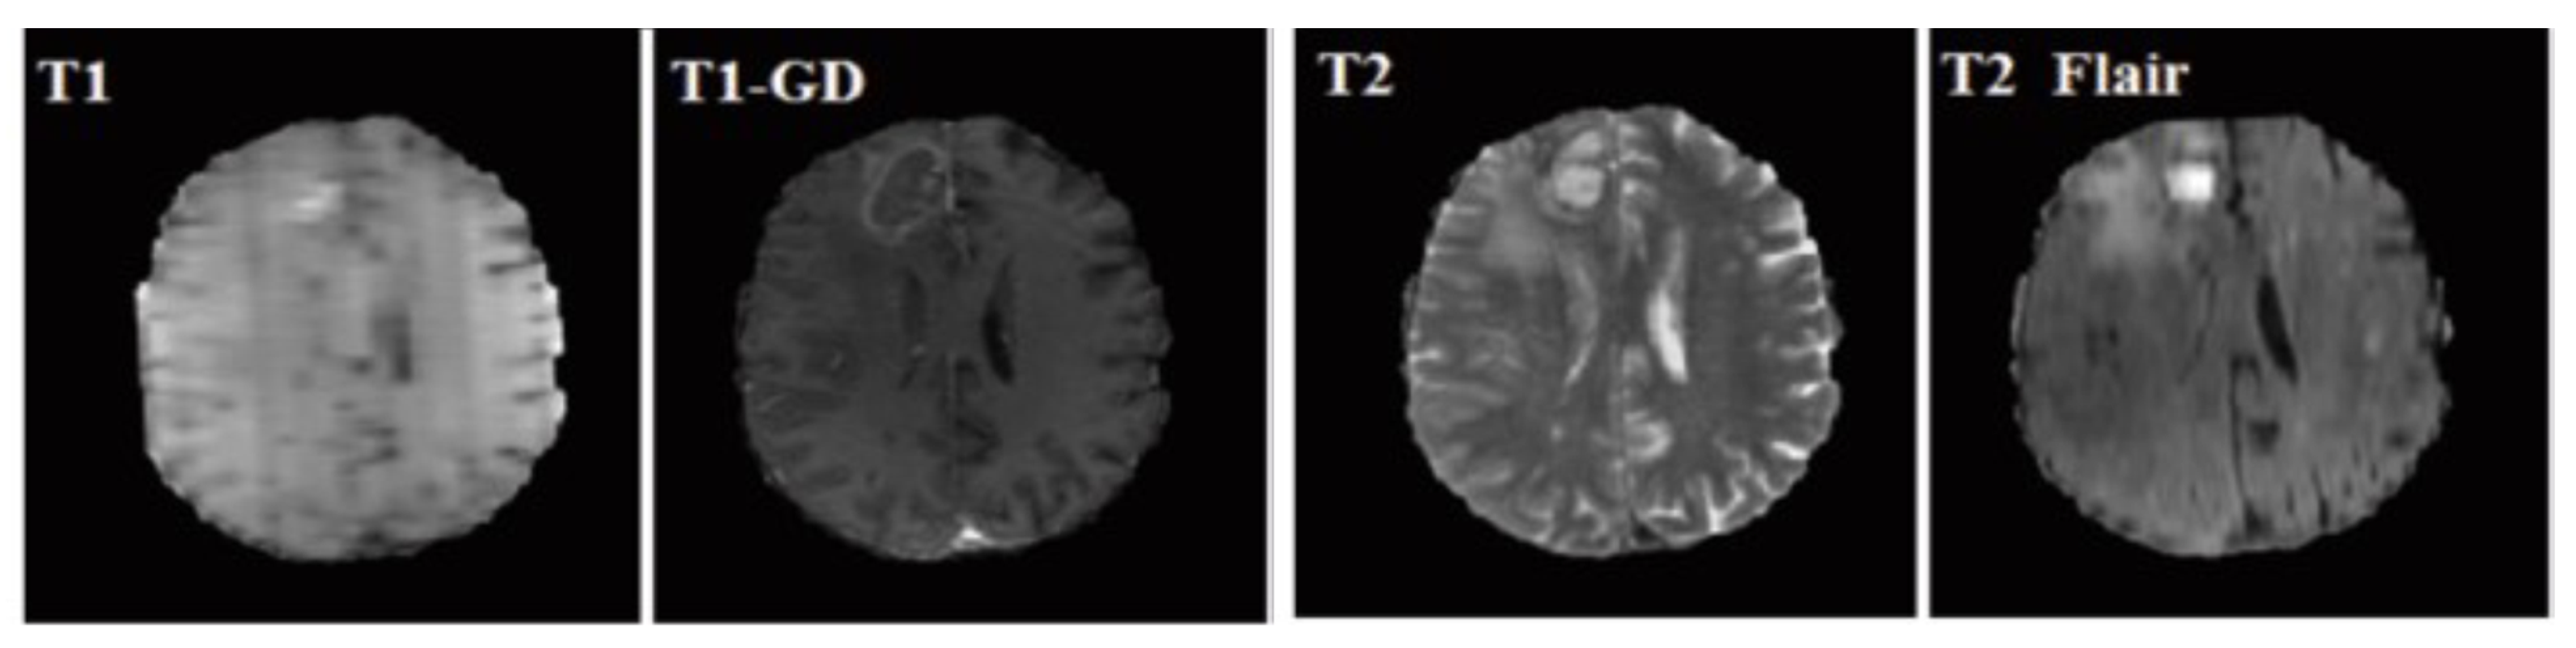

3.1. Material

| Input Image Size | 240*240*155 | |

| Training | # of HGG Images | 210 |

| # of LGG Images | 75 | |

| # of Test Dataset | 191 | |

| # of Validation Dataset | 66 | |